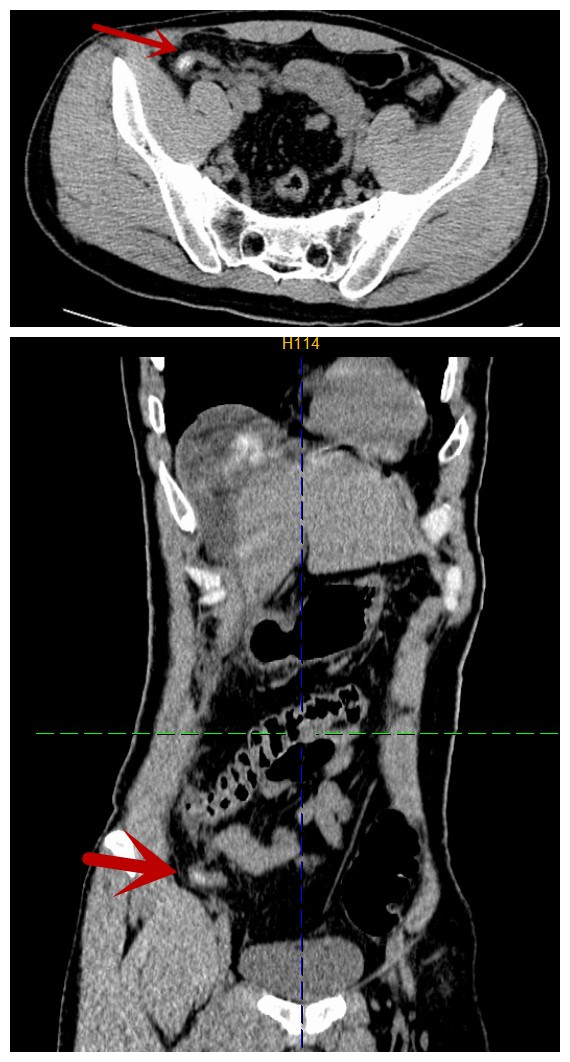

术前CT,箭头所指为阑尾肿胀伴有粪石

37岁男性患者唐某,因突发腹痛8小时于2026年1月8日急诊入院,呈刀割样剧烈疼痛,难以忍受。入院查体:急性病容,腹肌紧张,上腹部、右上下腹部压痛、反跳痛明显,肠鸣音减弱,约1次/分。腹膜炎体征明显,入院予急诊完善腹部CT检查提示:1.气腹,考虑消化道穿孔。2.阑尾粪石,并阑尾炎。3.腹腔积液。因病变部位不同,胃穿孔的病变解剖部位在上腹部,阑尾炎的病变解剖部位在右下腹,考虑要兼顾上下腹、充分显露手术部位等,传统手术需在腹壁开10cm-15cm的较长切口,手术创伤大,恢复慢。医生决定采用腹腔镜手术,只在腹壁打3-4个0.5cm-1.0cm戳孔就能完成手术。